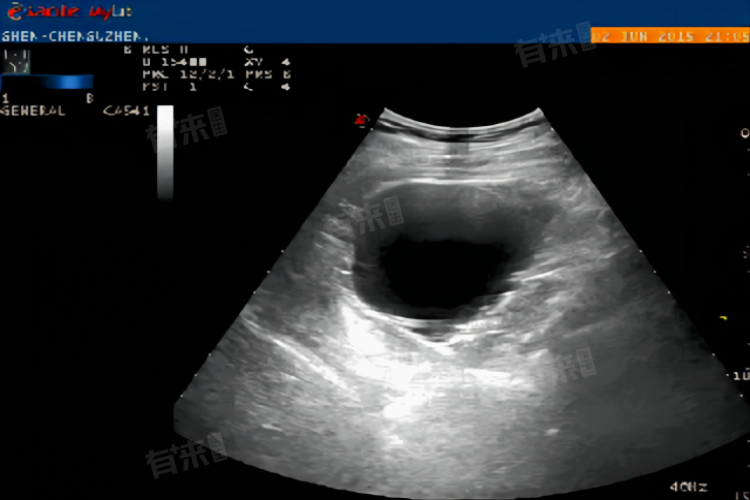

- 超声检查中显示的无回声区大小,是影响其转变为孕囊时间的关键因素。一般无回声区在5毫米左右时,大约需要10天才能变成孕囊,无回声区在10毫米左右时,可能只需3-5天能变成孕囊。

- 孕囊的质量和发育状况也直接决定从无回声区到孕囊的转变时间,如果孕囊发育良好,该过程可能会相对较快。但如果孕囊发育不佳,可能会出现空囊或流产等情况。受孕时间的早晚也会影响无回声区到孕囊的转变时间,受孕时间越早,无回声区转变为孕囊的时间可能就越短。